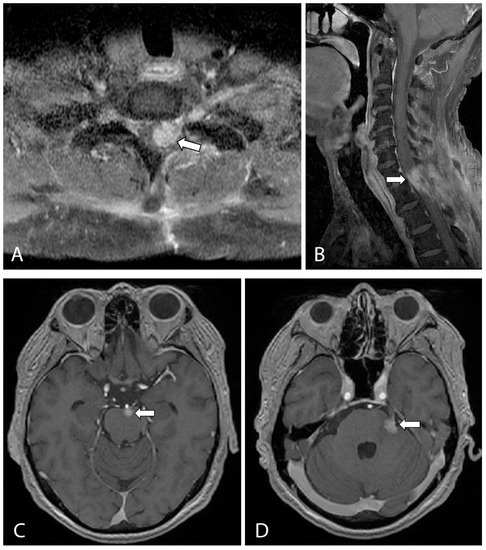

Post-operative recovery was unremarkable, and adjuvant radiation therapy was started 1 month after surgery. The patient received a total of 33 sessions of radiotherapy over the following 2 months. However, he developed worsening left-sided weakness and new left-sided facial pain within these 2 months. A follow-up MRI spine at 10 weeks post resection demonstrated an enlarging enhancing tumor in the left spinal cord at the levels of C7 and T1 and along the left T1/2 neural foramina. In addition, there were new enhancing lesions along the brainstem and pons, most prominent at the origin of the left trigeminal nerve trunk (Figure 4). Gamma knife surgery was performed for this lesion to reduce the left-sided facial pain.

Figure 4.

T1-weighted, fat-suppressed, contrast-enhanced axial (A) and sagittal (B) images from a follow-up MRI cervical spine showing a large enhancing lesion (arrows in (A,B)) consistent with local recurrence at the levels of C7 and T1, involving the spinal cord and left neural foramen. (C,D) T1-weighted, contrast-enhanced axial MRI of the brain showed new enhancing lesions at the anterior pons (arrow in (C)) and at the left anterolateral surface of the pons (arrow in (D)) involving the left trigeminal nerve, which accounted for the new left-sided facial pain.